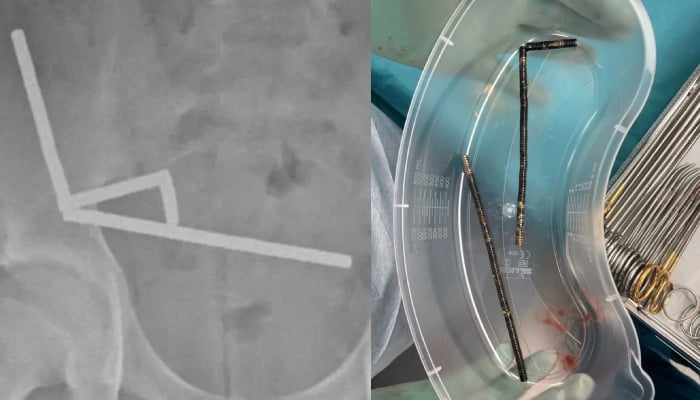

An X-ray showed the magnets had clumped together in four straight lines inside the child's intestines.

Doctors said the pressure of the magnets had caused necrosis, tissue death, in four areas of the boy's small bowel and caecum, which is part of the large intestine.

Surgeons operated to remove the dead tissue and retrieve the magnets, and the child was able to return home after eight days in hospital.